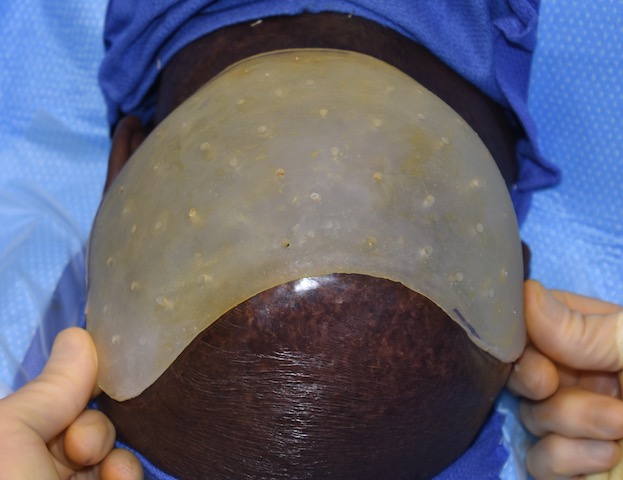

Patient 51

Desire for taller and rounder head shape.

Two stage custom skull implant augmentation technique.

Desire for taller and rounder head shape.

Two stage custom skull implant augmentation technique.